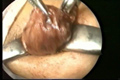

العمليات الجراحية التصويرية بالفيديو المنظاري

Videoendoskopik (Kapalı) Cerrahi

Ameliyat'tan Görüntüler